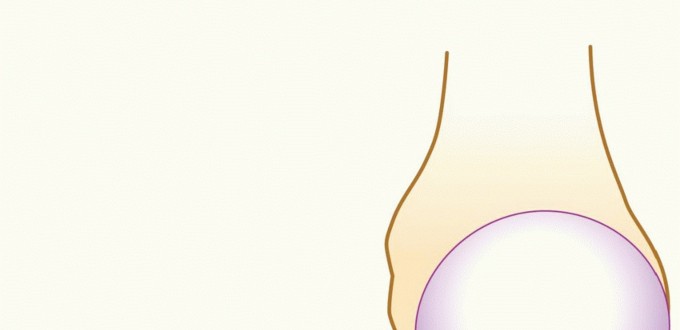

DEFINITION Panner Disease Panner disease is a condition in which there is compromised subchondral bone, poten…